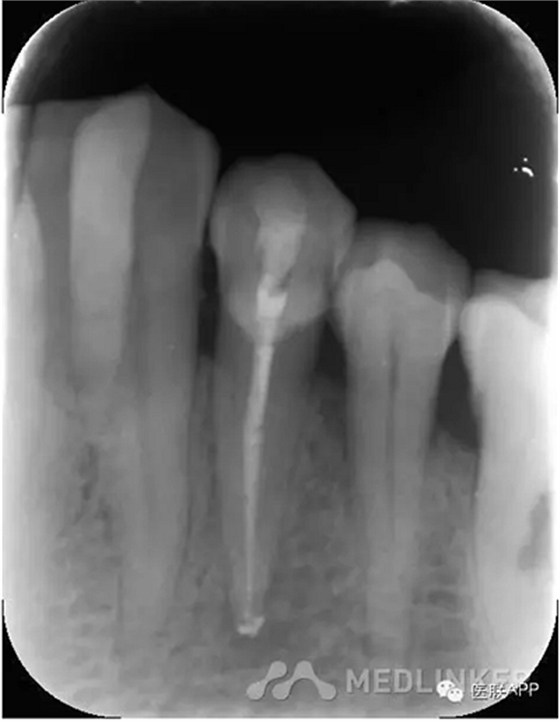

復(fù)診:去暫封,超聲蕩洗,干燥,試尖可,糊劑+熱牙膠根充,玻璃離子暫封,3月后復(fù)診,囑勿用患牙咬硬物。